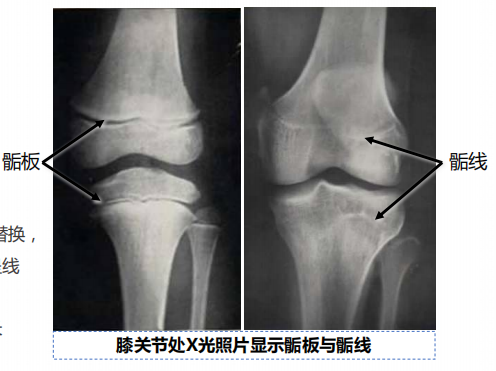

17~20 岁的青少年,骺板的软骨细胞停止分裂,骺软骨逐渐完全被骨组织取代,长骨的骨干和骨骺的骨组织连接融合形成薄层密质骨,在纵切面上为线性痕迹,称骺线(epiphyseal line),骺线形成意味着骨不能继续纵向生长。